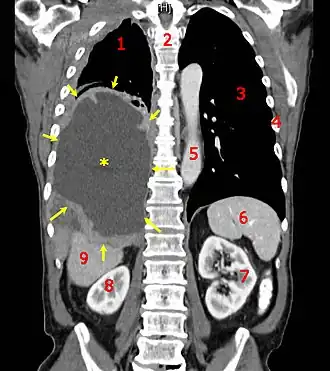

![]() Tomografia computerizată arată prezența mezotilomului malign Legendă: Mezoteliomul malign (cancer al mezoteliului cutiei toracice) este evidențiat prin săgeți de culoare galbenă; eufusiunea pleurală - prin stea galbenă. Cifrele indică: 1 și 3 plămâni, 2 coloană vertebrală, 4 coaste, 5 aortă, 6 splină, 7 - 8 rinichi, 9 ficat. | |